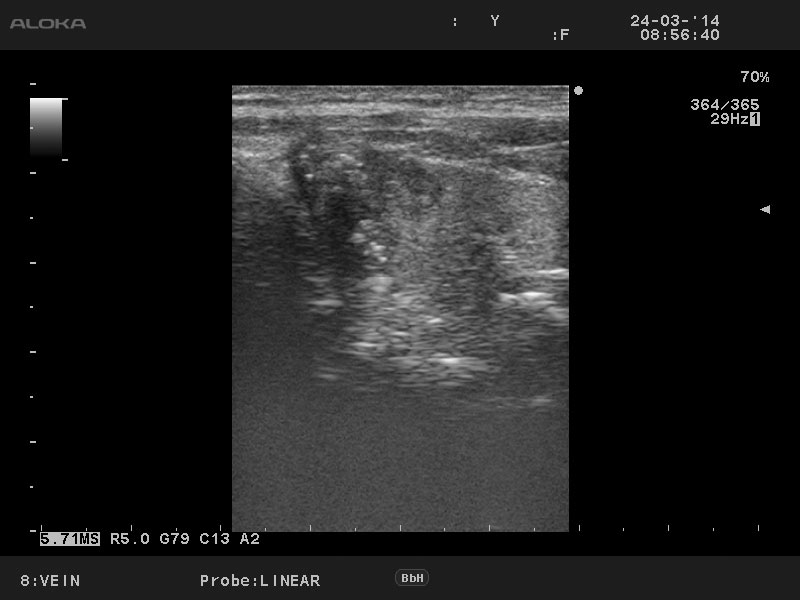

Папиллярный рак щитовидной железы

Мужчина 50 лет, жалоб нет.

Лимфоузел Диагноз доказан цитологически.